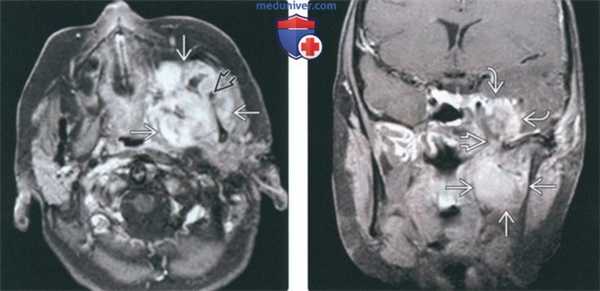

(Слева) На аксиальной МРТ (Т1 ВИ C+) в жевательном пространстве визуализируется лейомиосаркома высокой степени злокачественности, неравномерно накапливающая контраст и поражающая нижнюю челюсть. Большинство типов сарком жевательного пространства сложно дифференцировать в отсутствие костного или хондроидного матрикса.

(Справа) На корональной МРТ (Т1 ВИ С+ FS) у этого же пациента визуализируется контрастирующаяся опухоль с интракраниальным распространением через овальное отверстие а и поражением кавернозного синуса.в) Дифференциальная диагностика саркомы жевательного пространства:

(Слева) МРТ Т1ВИ FS с КУ, аксиальная проекция. Лейомиосаркома жевательного пространства высокой степени злокачественности. Опухоль неоднородно накапливает контраст и прорастает в нижнюю челюсть. Только по данным лучевой диагностики дифференцировать различные типы сарком невозможно, за исключением случаев обнаружения матрикса остео- или хондросаркомы.

(Справа) МРТ Т1ВИ FS с КУ, коронарная проекция, тот же пациент. Новообразование, накапливающее контраст, распространяется в полость черепа через овальное отверстие. Отсюда опухоль может прорастать в пещеристый синус.в) Дифференциальная диагностика: